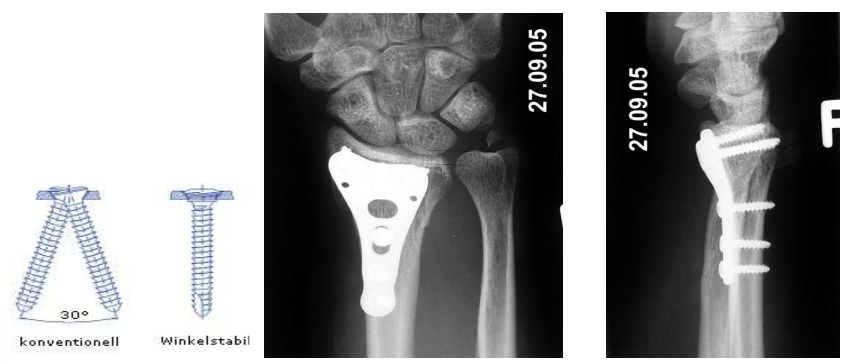

Operative Frakturbehandlung

Plattensysteme

Besonderheit Winkelstabile Platte

in Plattenlöchern gewinde eingebaut die zu Schrauben passen

Schrauben können sich weniger bewegen → stabilere Osteosynthese

Nachteil: zu stabil - Platten Wandern aus und Schrauben evtl die Knochen